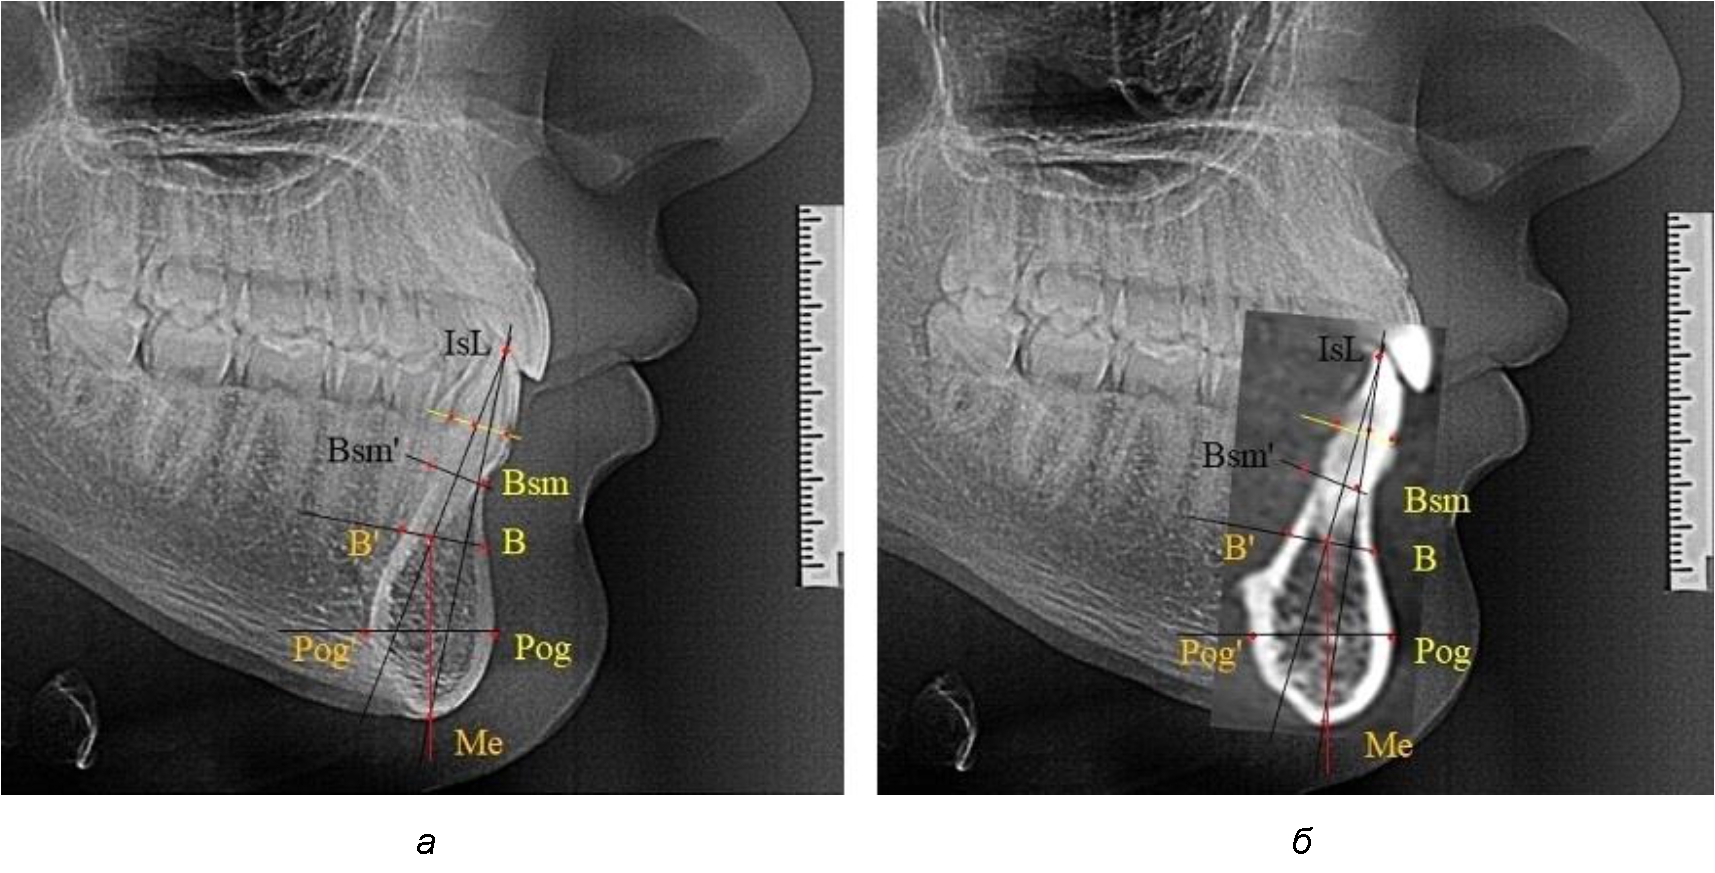

На режущем крае нижнечелюстного резцового сегмента устанавливалась точка, обозначаемая как IsL.

Определяли положение цервикальных точек резцов на вестибулярной и лингвальной поверхностях, которые соединяли цервикальной линией. Условная срединную вертикаль зуба соединяла резцовую точку IsL с серединой цервикальной линии и, как правило, доходила до апикальной точки, которую обозначали как Ap. Линия IsL–Ap определяла высоту зубоальвеолярной части резцового нижнечелюстного сегмента. Определяли высоту коронки и корня зуба. Кроме того, на вестибулярной поверхности зубочелюстного сегмента отмечали точку наибольшей вогнутости альвеолярной части, которая обозначалась как супраментальная точка Downs (Bsm). Измерялось расстояние IsL–Bsm, которое служило для определения проекции супраментальной точки Downs на язычную поверхность сегмента и обозначалась как точка Bsm'.

Проекцию верхушки корня резца на кость обозначалась как точка B нижнего апикального базиса по Schwarz. Соединяли апикальную точку с точкой нижнечелюстного апикального базиса линией, которая доходила до язычной поверхности подбородочного выступа и определяла положение точки B'. Таким образом, в зубоальвеолярной части сегмента выделялись две зоны: верхняя и нижняя, с последующим измерением по вертикали. При этом, как правило, верхняя зона была представлена компактной костной тканью, а в нижней зоне определялось наличие губчатой ткани между компактной пластинкой и стенкой альвеолы.

На нижнем контуре подбородочного выступа определяли положение ментальной точки Me. Линия, соединяющая апикальную точку с ментальной, определяла высоту подбородочного выступа тела нижней челюсти. Высота зубочелюстного сегмента IsL–Ме измерялась от резцовой до подбородочной точки. Вертикальная линия Ap–Me делила подбородочный выступ на две части: переднюю и заднюю (рис. 1).

Рис. 1. Ориентиры для исследования нативных препаратов (а) и рентгенограмм (б) резцового нижнечелюстного сегмента

Сагиттальные размеры зубоальвеолярной части сегмента определялись между точками Bsm и Bsm', в апикальной части сегмента – B и B'. В подбородочной части сегмента из передней выступающей точки подбородка Pog проводили линию перпендикулярно к линии Ар–Ме с определением точки Pog'. Расстояние Pog–Pog' определяло ширину подбородочного выступа.

При анализе боковых телерентгенограмм использовали фрагменты гнатической части, на которых оценивали вертикальные и сагиттальные параметры резцового нижнечелюстного сегмента, на который наносили те же ориентиры, что и при анализе нативных препаратов и их рентгенограмм.

При необходимости и/или возможности проведения КЛКТ-исследования проводили анализ с сопоставлением фрагмента, что повышало точность диагностических мероприятий (рис. 2).

Рис. 2. Фрагменты ТРГ с ориентирами для измерения параметров резцового сегмента (а) и с наложением фрагмента КЛКТ (б)